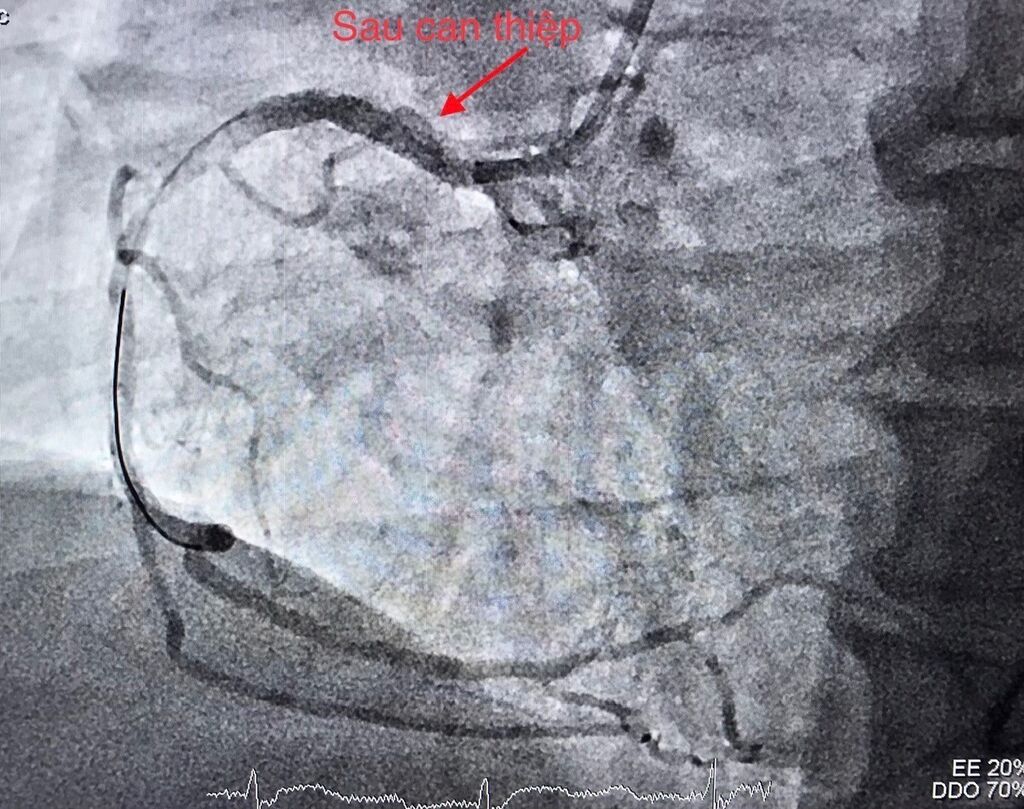

Kết quả CT scan não kiểm tra ngay tại phòng can thiệp cho thấy rõ chẩn đoán bệnh nhân bị nhồi máu não cấp là chính xác. Ngay lập tức, các bác sỹ Khoa Tim mạch đã chạy đua với thời gian, can thiệp tim mạch trong khoảng 40 phút. Bệnh nhân được nong động mạch vành bị tắc và tiến hành đặt giá đỡ (stent), giúp tái lập dòng máu nuôi tim.

Ngay sau đó, các bác sỹ can thiệp thông tắc động mạch não giữa bên phải. Các cục huyết khối được gắp ra, tái thông mạch máu bị tắc trong thời gian 20 phút.